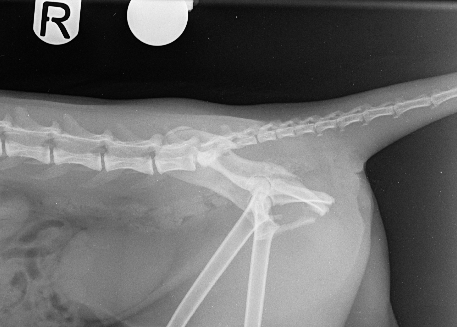

On presentation, she was unable to bear weight on her pelvic limbs. Withdrawal reflex and nociception were present, with normal proprioception in the right pelvic limb but delayed in the left. X-rays confirmed a right sacroiliac luxation, a left oblique ilium body fracture, a left ischium fracture involving the acetabulum, and bilateral pubic fractures (Figs. 1 and 2).

Fig. 2